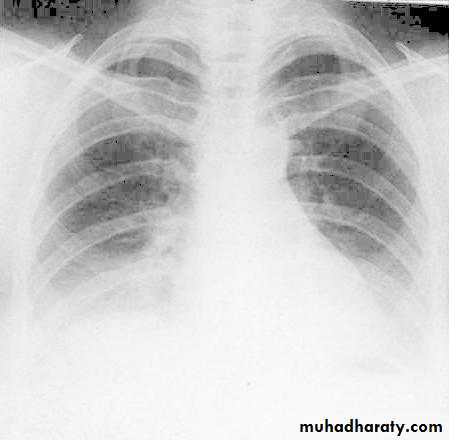

Rotation of the radiograph is assessed by judging the position of the clavicle heads and the thoracic spinous process.7) Good technique (amount of radiation )

The vertebral bodies are just visible through the cardiac shadow

PenetrationLow KV

High KV